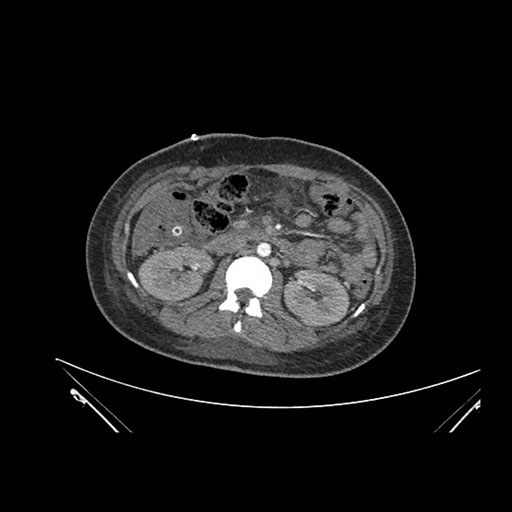

Imaging Analysis

Look through the patient's CT scan to identify any areas of concern for the necessary procedure.

Axial Arterial